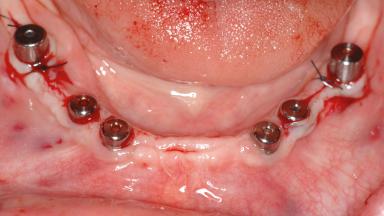

# of Implants 14

Type of Implants Two-Piece

Bone Augmentation Horizontal|Sinus Floor Elevation|Staged|Vertical

Augmentation Materials Autogenous chips|Autogenous block(s)|Xenogenous|Membrane